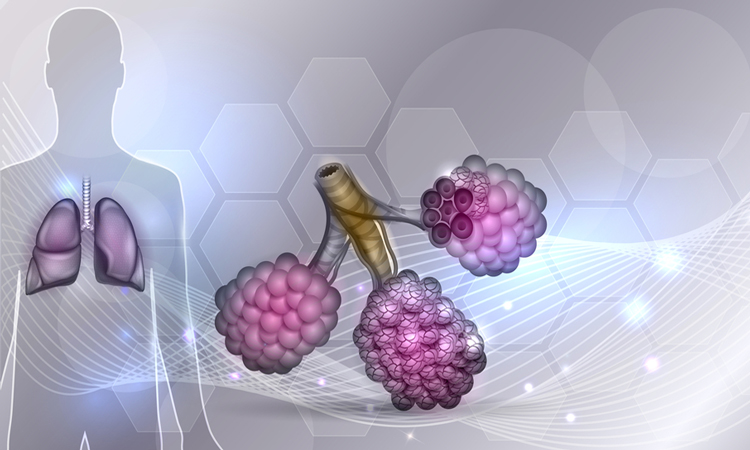

Vertex’s Kaftrio approved for use in Europe and made accessible on the NHS

The European Commission and European Medicines Agency have approved the triple combination Kaftrio for use in certain cystic fibrosis patients, triggering the drug to be accessible on the UK’s National Health Service.